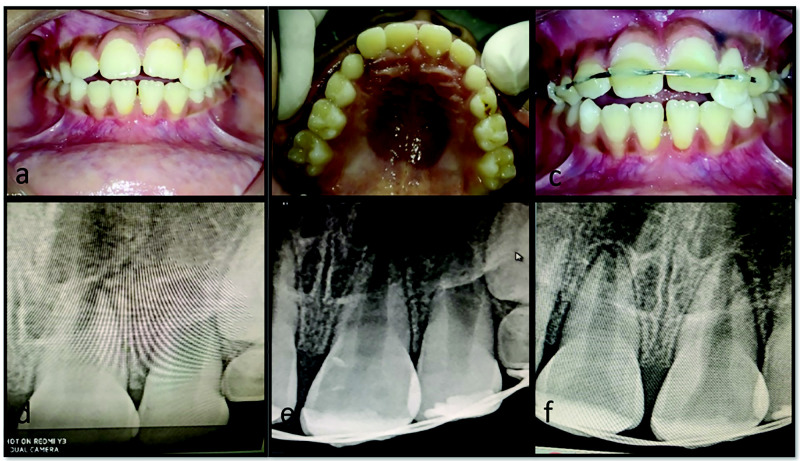

Dental injury is a common anesthesia-related adverse event, with a high incidence of damage to teeth and surrounding tissues during oro-endotracheal intubation. Poor oral hygiene, compromised periodontium, faulty or loose prosthesis, proclined maxillary incisors along with increased difficulty level of airway management, improper use of laryngoscope, and use of maxillary anterior teeth as a fulcrum for achieving accessibility to the airway are all risk factors for iatrogenic dental injury. This type of injury provides additional physical and psychological trauma to patients who have already undergone medical surgical procedures. The consequences of such mishaps might potentially result in medico-legal suits and financial claims. The present case series described three cases of managing iatrogenic dental lesions during oro-endotracheal intubation, after obtaining written informed consent, as well as methods for preventing such accidental injuries. This study emphasized the importance of collaboration between medical and dental professionals in preventing and successfully managing accidental dental injuries.